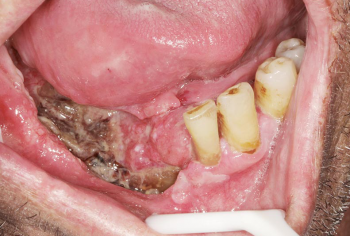

Les cancers des voies aérodigestives supérieures (VADS) comprennent d’une part les cancers de la lèvre, de la bouche et du...

L’addiction est une maladie complexe, d’un organe complexe, le cerveau, chez un mammifère complexe, dans une société complexe en évolution,...